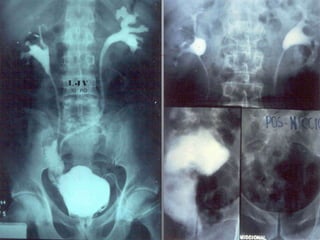

Câncer de Bexiga Estudos de imagens Diagnóstico Ultrassonografia Urografia excretora Estadiamento CT RNM Rx tórax  Cistoscopia + biópsia + biópsias randomizadas

CISTOGRAMA / TUMOR DE BEXIGA

Urografia excretora / cistograma